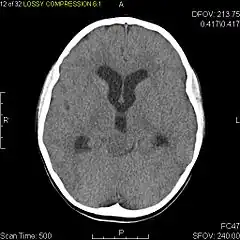

Axial non-contrast CT in a nine-year-old girl showing a slightly hypodense mass in the tectum of the brainstem, compressing the aqueduct of Sylvius and causing obstructive hydrocephalus -

Usually – depending on the interview of the patient and after a clinical exam which includes a neurological exam and an ophthalmological exam – a CT scan and/or an MRI scan will be performed to confirm the presence of a tumor. They are usually easily distinguishable from normal brain structures using these imaging techniques. A special dye may be injected into a vein before these scans to provide contrast and make tumors easier to identify. Pilocytic astrocytomas are typically clearly visible on such scans, but it is often difficult to say based on imaging alone what type of tumor is present.